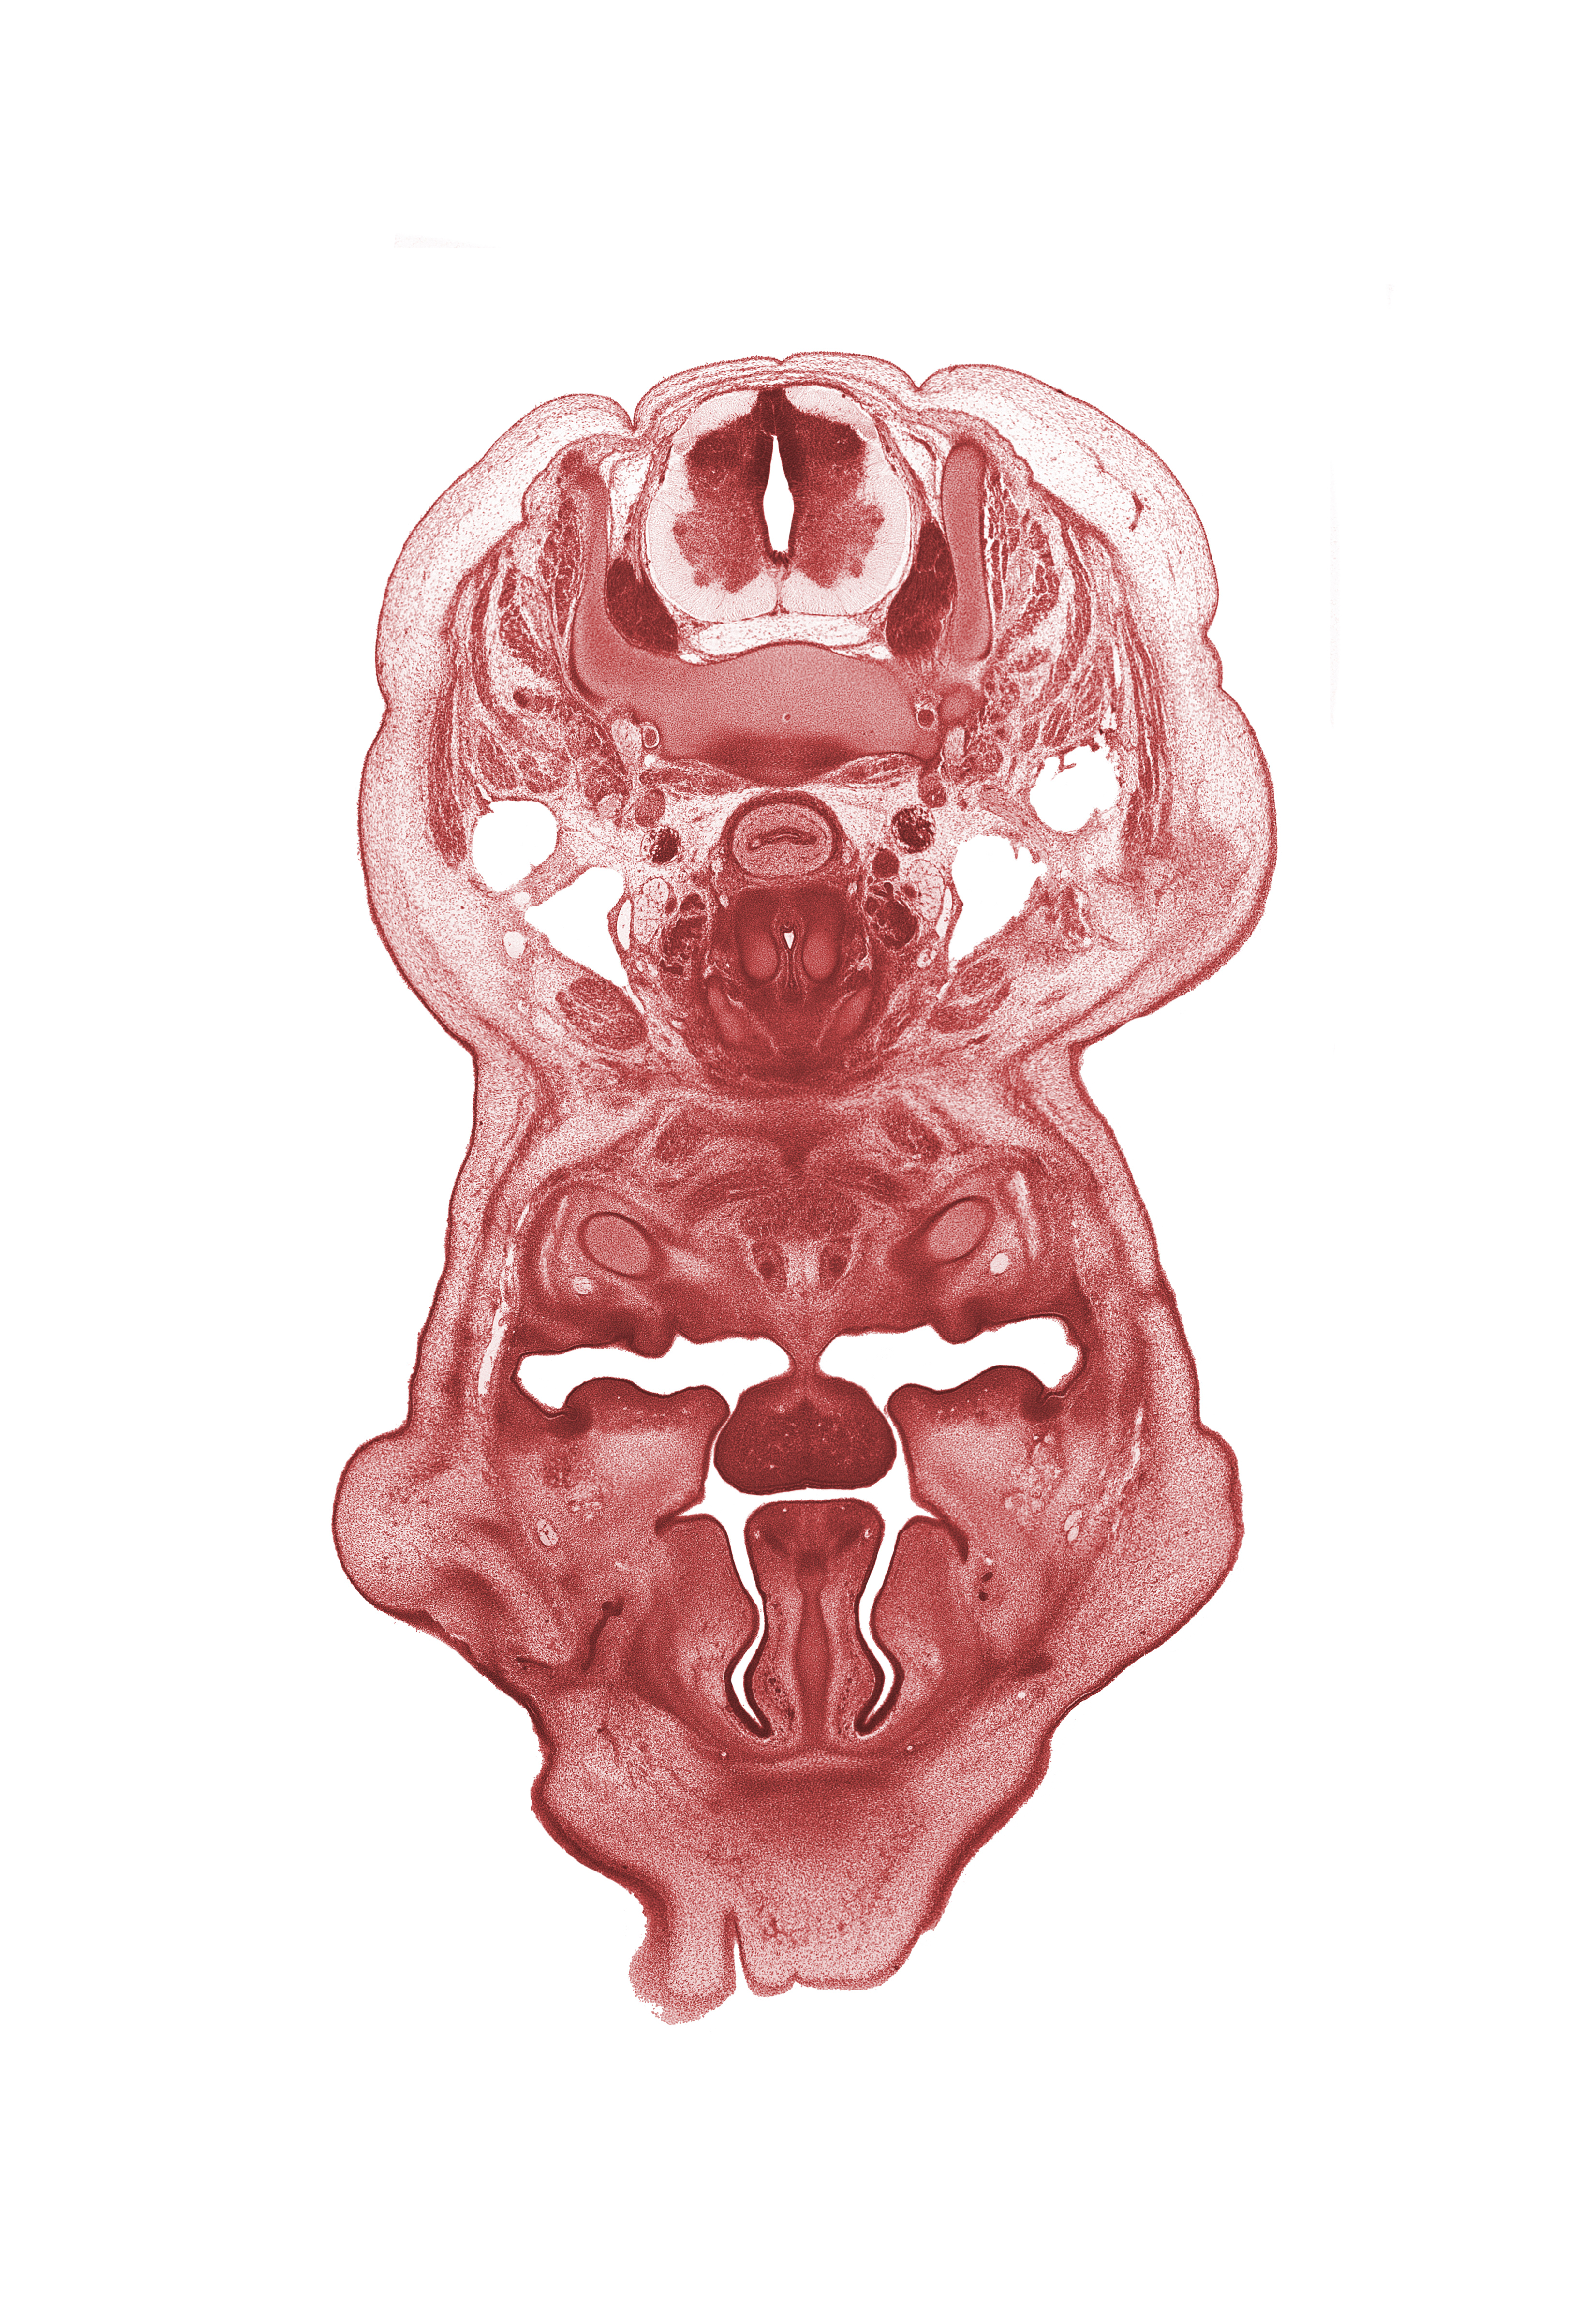

Carnegie Embryo #4090 | Location: 12-11

Keywords: C-6 spinal ganglion, choana, frenulum of tongue, genioglossus muscle, geniohyoid muscle, inferior meatus, inferior nasal concha, internal jugular vein, interorbital ligament, jugular lymph sac, longus cervicis muscle, nasolacrimal duct, neural arch, oral cavity, palatine shelf, pharyngeal arch 1 cartilage (Meckel), platysma muscle, sternocleidomastoid muscle, thyroid cartilage, trapezius muscle

Source: The Virtual Human Embryo.